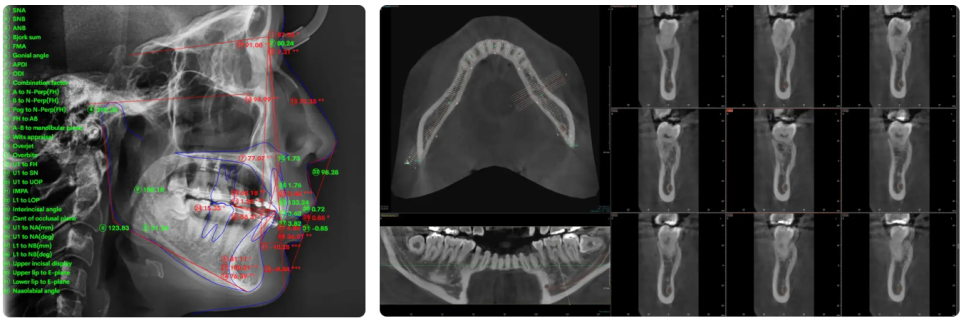

잇몸과 뼈,

이 두 가지가 기준이 됩니다.

벌어진치아교정

다음으로 겉으로 보기에는

잘 드러나지 않는 부분입니다.

치아는 잇몸과 뼈에 의해

지지되는 구조로 이어져 있는데요.

그래서 이 지지 기반이 약해지면

치아 위치가 조금씩 달라지면서

사이에 공간이 생기게 되죠.